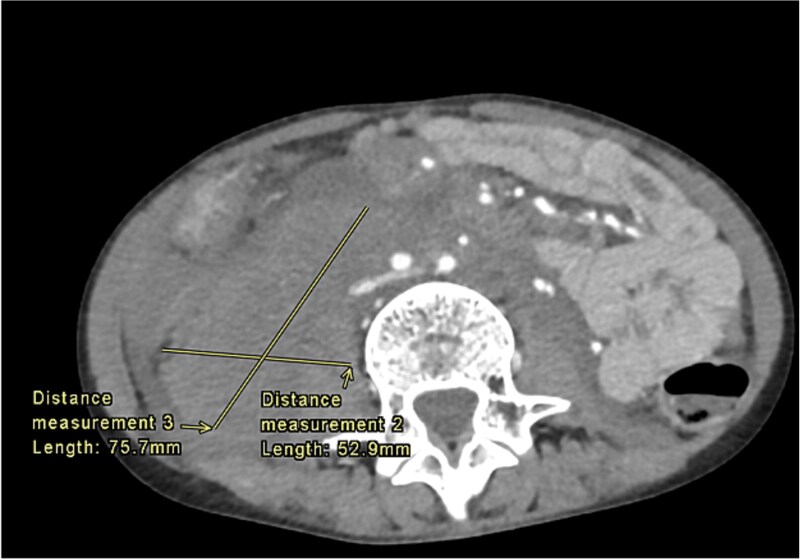

ehers - danlos综合征(EDS)包括一系列遗传性结缔组织疾病,其中后凸性脊柱侧凸变体是一种罕见的表现。我们提出一个病例11岁的男性诊断为埃勒斯-丹洛斯综合征VI(后凸侧凸变型)谁提出了急性发作的症状提示血管出血。尽管这种情况在儿科人群中很少见,但一个多学科团队迅速介入并彻底评估了紧急情况。影像学检查显示腹膜后出血,从T10延伸到下骶椎,并伴有一个相当大的动脉瘤,紧挨着腹腔动脉。经评估,团队选择保守管理,强调在重症监护病房警惕监测和疼痛管理。该病例强调了针对性管理和研究的重要性,以优化结果并减少以血管出血为表现的ehers - danlos综合征后凸变型儿科患者的并发症。

Ehlers-Danlos syndrome (EDS) encompasses a spectrum of heritable connective tissue disorders, with the Kyphoscoliotic variant representing a rare manifestation. We present a case of an 11-year-old male diagnosed with Ehlers-Danlos Syndrome VI (Kyphoscoliotic Variant) who presented with an acute onset of symptoms suggestive of vascular hemorrhage. Despite the rarity of such presentations in pediatric populations, a multidisciplinary team swiftly intervened and thoroughly evaluated the emergent situation. Imaging studies revealed a retroperitoneal hemorrhage extending from the T10 to lower sacral vertebra, along with a sizable aneurysm closely juxtaposed to the celiac artery. After evaluation, the team opted for conservative management, emphasizing vigilant monitoring and pain management in the intensive care unit. This case underscores the significance of tailored management and research to optimize outcomes and reduce complications in pediatric patients with kyphoscoliotic variant of Ehlers-Danlos syndrome presenting with vascular hemorrhage.